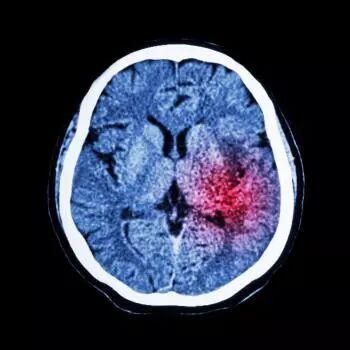

世界预防中风日是在2004年6月24日在加拿大温哥华举行的第五届“世界中风研讨会”,订立每年5月25日为世界预防中风日,加强人们认识中风及相关问题,预防中风。中风是脑血管出现问题,令脑细胞失去血液、氧气和养分供应,最终令脑细胞受损或死亡,继而影响到该部分脑细胞所控制的功能,例如活动及语言机能,妨碍病患者自我照顾能力。

中风是一种以脑部缺血及出血性损伤症状为主要临床表现的疾病,多发于中老年群体。中国每年会有150万人因为中风而去世,美国每年新增或者复发的中风患者达到近80万。中风发生突然,幸存者中约80%会出现不同程度的残疾,包括瘫痪、偏瘫、失语等。

脑中风又叫“脑卒中”,是由于各种诱发因素引起脑内动脉狭窄、闭塞或破裂,一般分为缺血性脑中风和出血性脑中风。简单来说,脑血管堵塞了(缺血),或者破裂了(出血),都叫做脑中风。

中风主要包括出血性脑中风和缺血性脑中风。其中,缺血性脑中风最常见 (87%),主要是由于大脑血管堵塞,富含氧气的血液流通不畅形成凝块后导致的。而出血性中风则是因为大脑血管破裂引发的。